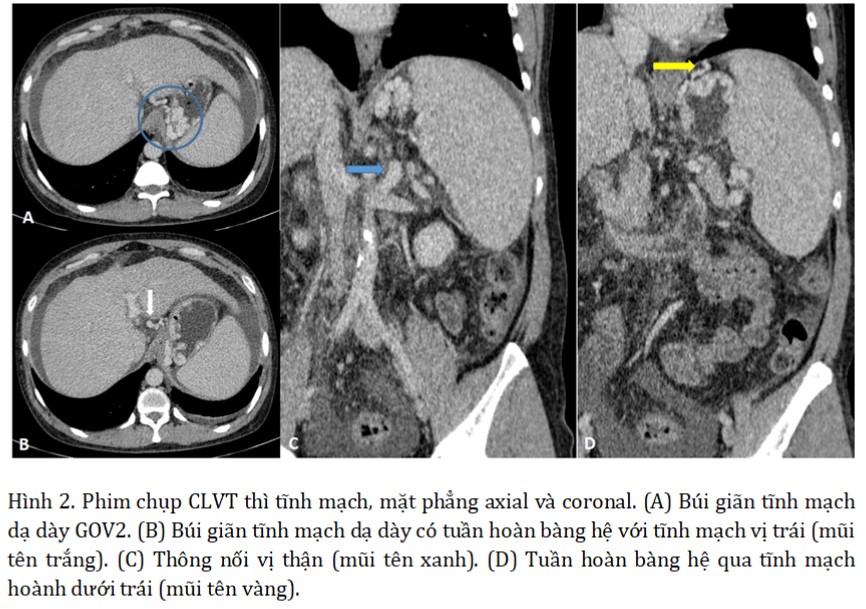

Phim chụp CLVT của bệnh nhân 1 tháng trước cho thấy nhiều búi giãn tĩnh mạch ngoằn ngoèo ở phình vị dạ dày có nhiều tuần hoàn bàng hệ đổ về tĩnh mạch chủ dưới qua hệ tĩnh mạch vị hoành (gastrophrenic venous system), có thông nối vị - thận (gastrorenal shunt - GRS). Đường kính chỗ lớn nhất của thông nối là 13 mm. Đây là yếu tố quyết định cho phép lựa chọn phương pháp BRTO/PARTO.